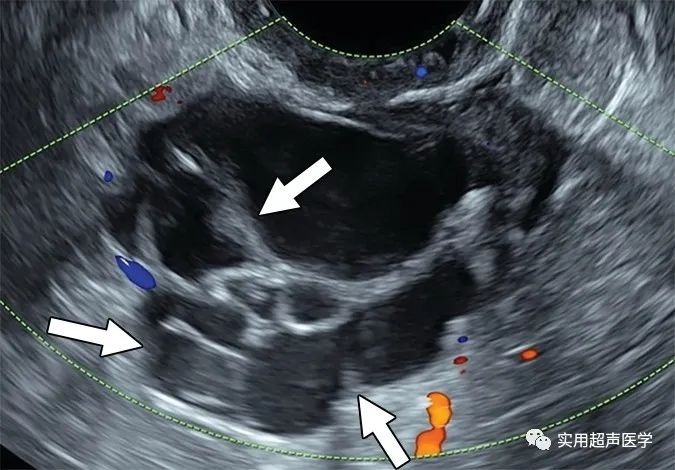

68岁女性腹胀,左卵巢交界性浆液性囊腺瘤。彩色多普勒超声图像显示多房囊肿,内壁和分隔不规则(箭头),无实性成分,符合卵巢-附件报告和数据系统 (O-RADS) 4 类病变。当多房囊肿的内壁或分隔不规则时,代表内部血管和大小的颜色评分 (CS) 无助于 O-RADS 风险评估。